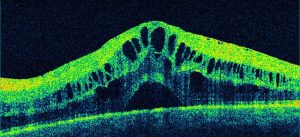

La tomografia a coerenza ottica (OCT) è un test di imaging non invasivo che utilizza le onde di luce per scattare foto della retina, e in particolare della macula. La macula è una parte della retina deputata alla visione a colori e ad alta definizione.

Con l’OCT possono essere analizzati e mappati tutti gli strati retinici, inoltre è possibile rilevare lo spessore retinico. Questi dati aiutano a effettuare una corretta diagnosi e a fornire delle indicazioni per il trattamento del glaucoma e delle patologie retiniche, malattie come la degenerazione maculare senile e la retinopatia diabetica.

Se in atto è presente o è stata presente una di queste condizioni retiniche è importante eseguire l’OCT.